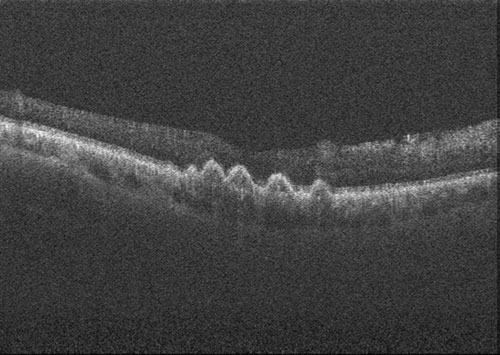

浮腫